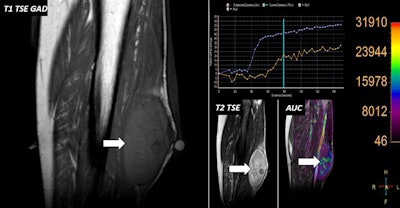

70-year-old woman with neurofibromatosis and palpable lump in her leg. MRI confirmed the presence of a well-defined lesion with scarce enhancement on postgadolinium images (white arrows). DCE-MRI analysis showed fast wash-in (blue curve) within lesion compared with tibial anterior muscle used as internal reference (orange curve) as well as higher relative enhancement values.Lipomas are one of the most common lesion types to show low signal intensity on DWI and low ADC values. Despite showing lower ADC values than malignant sarcomas, lipomas are benign, the authors explained. These low ADC values are because the DWI sequence uses fat suppression pulses that nullify the signal on both low and high b-values from lipomas. Also, lipomas are composed in 95% of cases by fat vacuoles with scarce presence of water molecules (which are responsible for any kind of signal intensity on DWI).